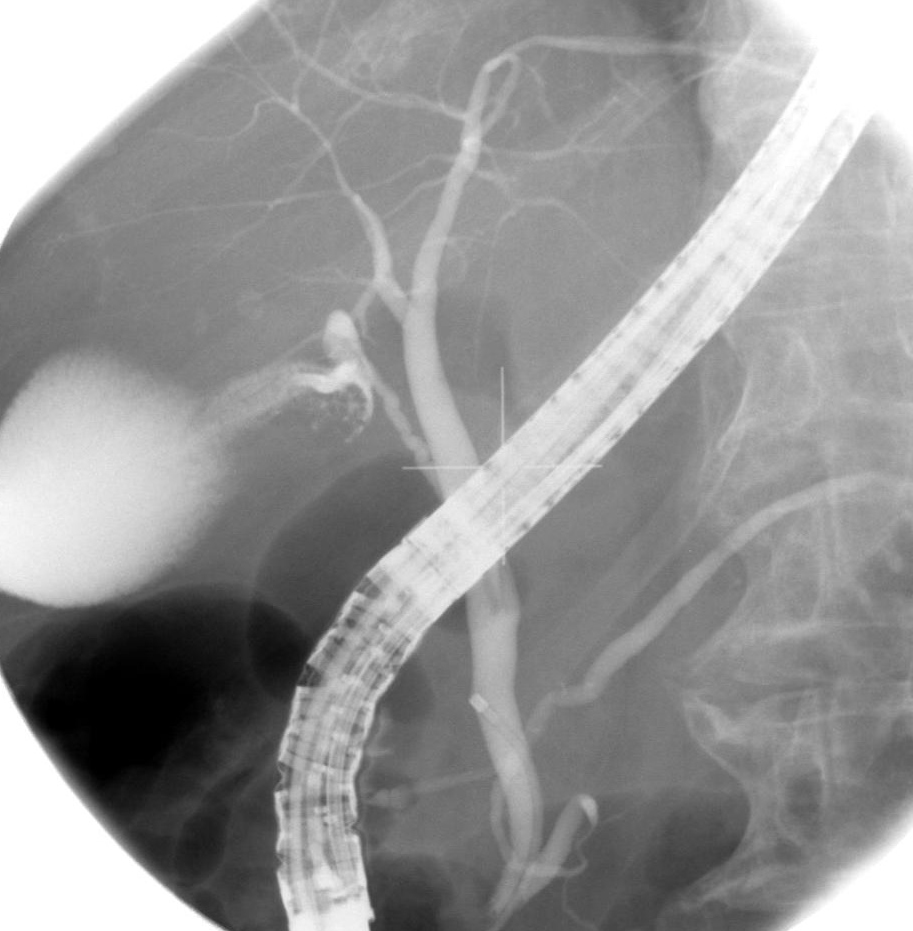

CT cholangio par perfusion

intraveineuse de Bilicospine , recontruction

spaciale en 2D : Canal choledoque , canal

cystique et voies biliaire intrahepatique en

voyaient tres nette . La vesicule biliaire dilate a

bord lisse et tres nette se envoyant |

Image radiologique normales des voies

biliaire intrahepatique , canal hepatique et canal

cholodoque en voyaient bien . Image de la

vesicule biliaire est meme en vue : CT

cholagiographie de recontruction images en 3D ( OAG

) |

| Conduit hepatique droit :

C'est images des canal de voies biliaire

du segment V , VI , VII , VIII |

| Canal hepatique gauche

: Images des canal de voie biliaire des

segment I , II ,III, et IV |

| Canal cystique et canal

choledoque sont en vue bien |